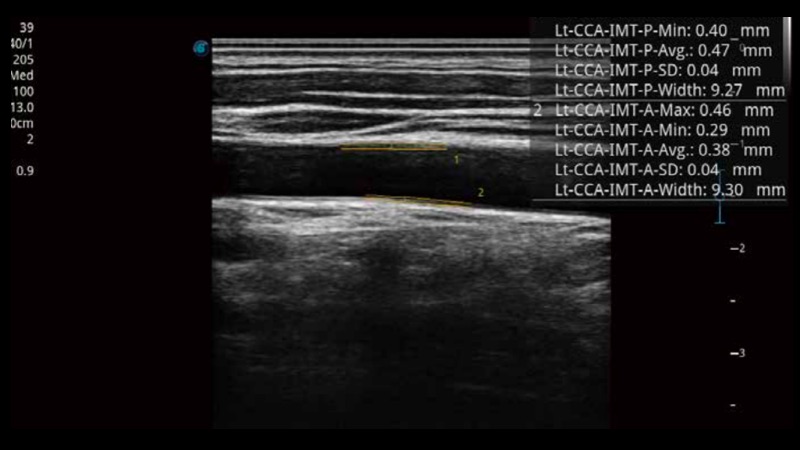

自动识别前后壁内膜厚度,为心血管疾病早期评估提供快速准确依据。